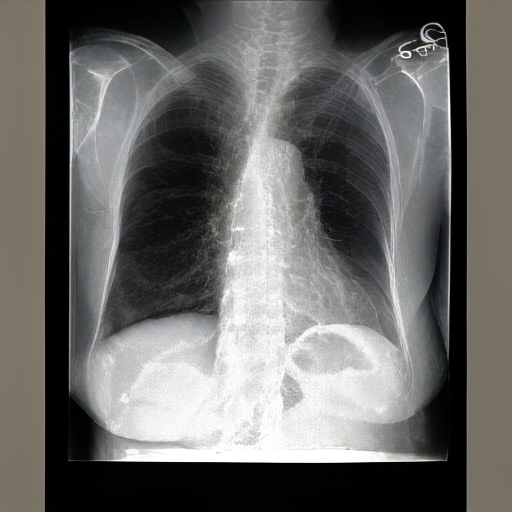

The lungs are well expanded and appear clear. Cardiomediastinal silhouette and hilar contours are otherwise unremarkable. No pleural effusion, or pneumonia pneumothorax. IMPRESSION: No acute cardiopulmonary process or evidence of traumatic injury or acute aortic abnormality are. Consider CT to be in etiology and sensitivity for fractures.

PA and lateral chest radiographs demonstrate hyperinflated lungs, suggestive of COPD. Otherwise, there is no focal consolidation, pleural effusion, or pneumothorax. The cardiomediastinal and hilar contours are normal. No acute osseous abnormalities are detected. No acute cardiopulmonary abnormality is present. Postsurgical changes are noted in the upper abdomen.

FINDINGS: The lungs are hyperinflated but without focal consolidation. No pleural effusion or pneumothorax is seen. The cardiac and mediastinal silhouettes are unremarkable. No pulmonary edema is seen. Bilateral hila are unremarkable. IMPRESSION: Lungs remain hyperinflated, suggesting possible COPD. No focal consolidation is seen.